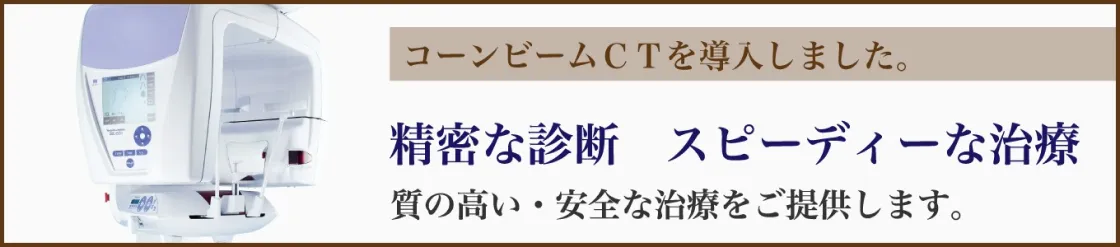

コーンビームCTスキャン

(ベラビューエポックス3Dfα)

従来機に比べ照射範囲が大きく、歯列の形に添った動きをするため、放射線感受性が高い唾液腺やリンパ節などを被爆させずに撮影が可能になりました。このことにより最大50%の被曝量低減を実現しています。

ベラビューエポックス3Dfα

当院が導入したコーンビームCTは、世界で初めて歯科用コーンビームCTを開発したモリタ社製のベラビューエポックス3Dfαです。従来機に比べ照射範囲が大きいにも関わらす、歯列の形に添った動きをするために、放射線感受性が高い唾液腺やリンパ節などを被爆させずに撮影が可能になりました。このことにより最大50%の被曝量低減を実現しています。

放射線被ばく線量

歯科用CTで生じる放射線量は、非常に微量です。当院のコーンビームCTは、CTスキャン1回あたりの放射線量は0.02~0.12mSvです。これは胸部CT撮影(1回)、胃のX線透視検査(1回)よりも格段に少ないです。 私たちは日常の生活の中でも自然放射線を浴びています。1人あたりの自然放射線は年間約2.1mSv(日本平均)です。CT撮影に関して人体への心配はありません。安全に撮影できますので、安心してご相談ください。